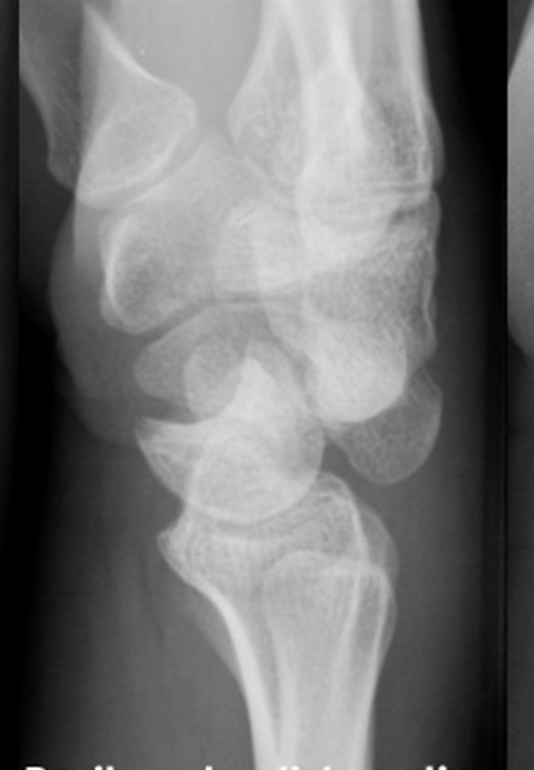

1. Can you describe this radiograph?

2. How many Gilula lines can you see in this image?

The image shows dorsal dislocation of the capitate which should be congruous with the cup of the lunate.

## Perilunate Dislocations and Fracture-Dislocations The lunate, which is normally securely attached to the distal radius by ligamentous attachments, is commonly referred to as the โcarpal keystone.โ ## Greater Arc Injury Greater arc injury passes through the scaphoid, capitate, triquetrum, or distal radial styloid and often results in transscaphoid, transcapitate, or transradial styloid perilunate fracture-dislocations.  ## Lesser Arc Injury Lesser arc injury follows a curved path around the lunate, involving only the capsuloligamentous tissues through the scapholunate ligament, midcarpal joint, and lunotriquetral ligaments and results in perilunate and lunate dislocations. The most common injury is transscaphoid perilunate fracture-dislocation. Disruption of the normal kinematics and stability of the carpal row lead to acute failure with a predictable pattern of posttraumatic changes.  ## Mechanism of Injury Perilunate injuries: Axial load is applied to the thenar eminence, forcing the wrist into extension. Injury progresses through several stages (Mayfield progression): It usually begins radially through the body of scaphoid (fracture) or through scapholunate interval (dissociation), although both are possible in the same injury (rare). Force is then transmitted ulnarly through the space of Poirier (between the lunate and capitate). Subsequently, force transmission disrupts the lunotriquetral articulation. This results in dorsal dislocation of the capitate and rest of the carpus relative to the lunate. Finally, the lunate can dislocate volarly out of the lunate fossa of the distal radius, in which case it is called the lunate dislocation. In a lunate dislocation, the proximal part of the capitate sits in the lunate fossa. ## Clinical Evaluation Scapholunate or perilunate injuries typically cause tenderness just distal to Lister tubercle. Swelling is generalized about the wrist with variable dorsal prominence of the entire carpus in cases of dorsal perilunate dislocations. ## Radiographic Evaluation PA, lateral, and oblique views should be obtained to confirm the diagnosis and rule out associated injuries. A CT scan may be useful in further defining the injury pattern. * **PA View** The dislocated lunate appears to be wedge-shaped and more triangular, with an elongated volar lip. Loss of normal carpal colinear โGilula linesโ and abnormal widening of the scapholunate interval >3 mm are noted. Look for associated fractures, such as โtransscaphoidโ injuries.  * **Lateral View** Most important view. Carefully look at the outline of the capitate and lunate. The โspilled teacup signโ occurs with volar dislocation of the lunate. A clenched-fist PA view obtained after closed reduction of the midcarpal joint is useful for checking residual scapholunate or lunotriquetral dissociation as well as fractures.  ## Classification (Mayfield) | Stage | Description | | :------ | :----------------------------------------------------------------------------------------------------------------------------------------------------------------------------------------------------------------------- | | Stage I | Disruption of the scapholunate joint: The radioscapholunate and interosseous scapholunate ligaments are disrupted. | | Stage II | Disruption of the midcarpal (capitolunate) joint: The radioscaphocapitate ligament is disrupted. | | Stage III | Disruption of the lunotriquetral joint: The distal limb of the radiolunotriquetral ligament and the ulnotriquetrocapitate complex is disrupted. | | Stage IV | Disruption of the radiolunate joint: The dorsal radiolunotriquetral ligament is disrupted, ultimately causing volar dislocation of the lunate. | ## Treatment Closed reduction should be performed with adequate sedation. Closed reduction of lunate dislocations is frequently unsuccessful. Early surgical reconstruction is performed if swelling allows. Immediate surgery including open carpal tunnel release is needed if there are progressive signs of median nerve compromise. Most transscaphoid perilunate dislocations are best treated by open volar and dorsal reduction and repair of the injured structures. Open repair should be supplemented by pin fixation while ligaments heal. Delayed reconstruction is indicated if early intervention is not feasible. ## Complications * Median neuropathy may result from carpal tunnel compression, necessitating surgical release. * Posttraumatic arthritis may result from the initial injury or secondarily from small, retained osseous fragments and cartilage damage. * Chronic perilunate injury may result from untreated or inadequately treated dislocation or fracture-dislocation resulting in chronic pain, instability, and wrist deformity, often associated with tendon rupture or increasing nerve symptoms. * Recurrent instability may necessitate ligament reconstruction with capsular augmentation. * If recurrent instability persists, lunotriquetral fusion may be necessary, with possible concomitant ulnar shortening to tension the volar ulnocarpal ligaments.